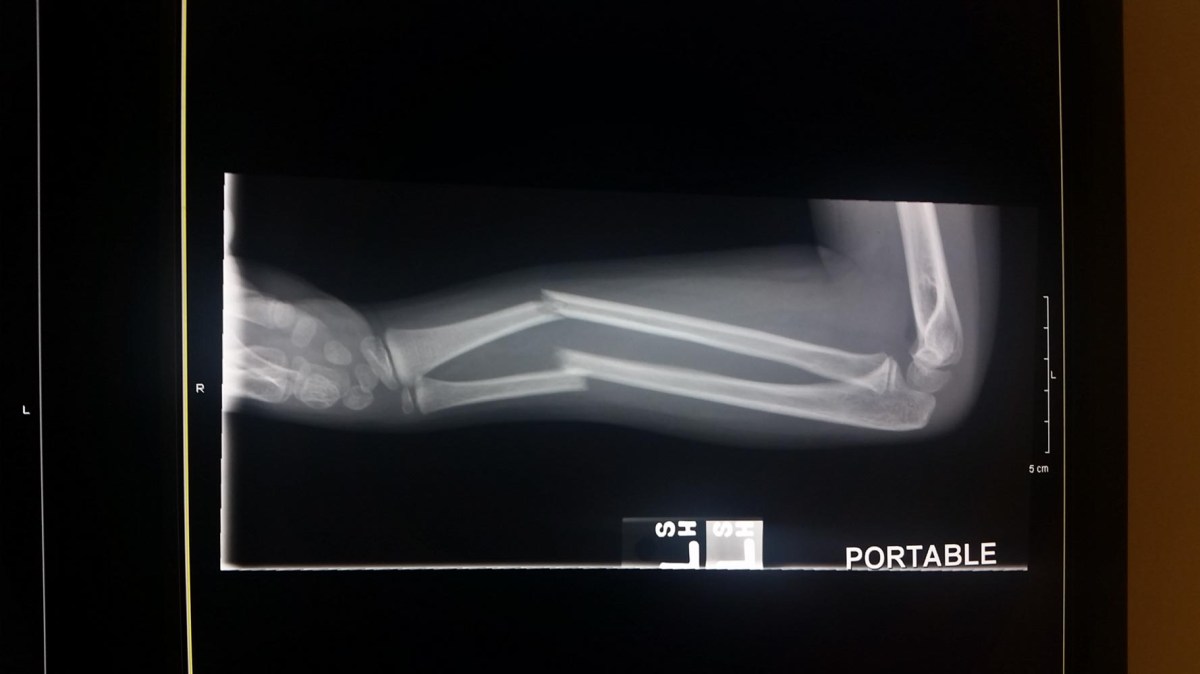

At the ER they put us back into a room right away. From there however it took forever. We ended up being their for 6 hours. She had multiple x-rays, they reset her arm and finally put a splint on it. It turns out she broke both bones in her arm and the doctor was concerned she may need surgery. We are still not sure if she’ll need surgery or not. The orthopedic doctor says it looks pretty good but we wont know for sure until she gets her cast off in 3 weeks. It has been quite an experience.